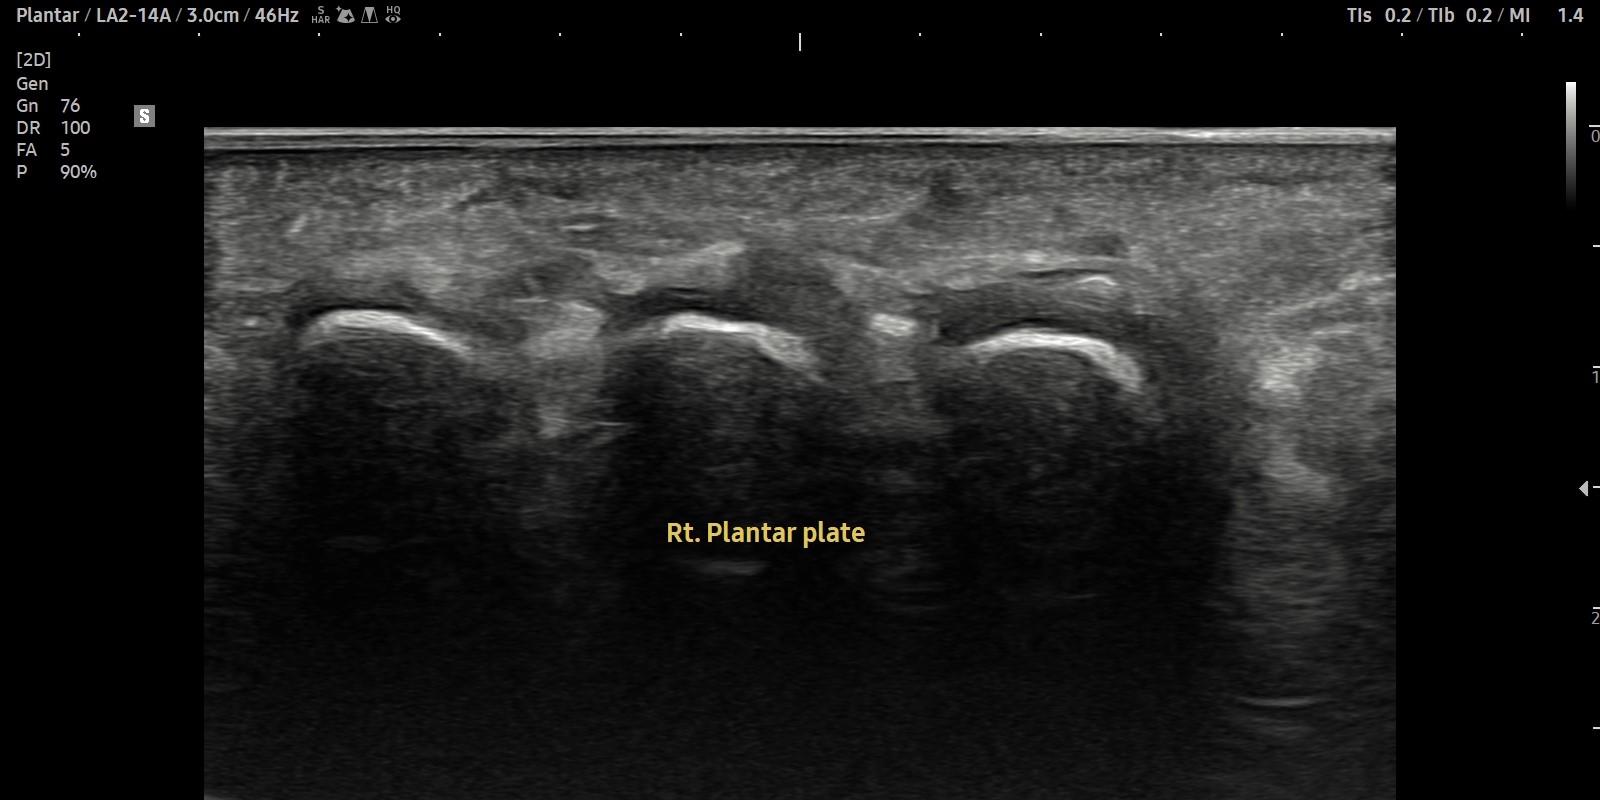

- 치료기간 : 2025. 5. 1. ~ 2025. 6. 14

- 치료횟수 : 10 회

[치료 전]

[치료 후]